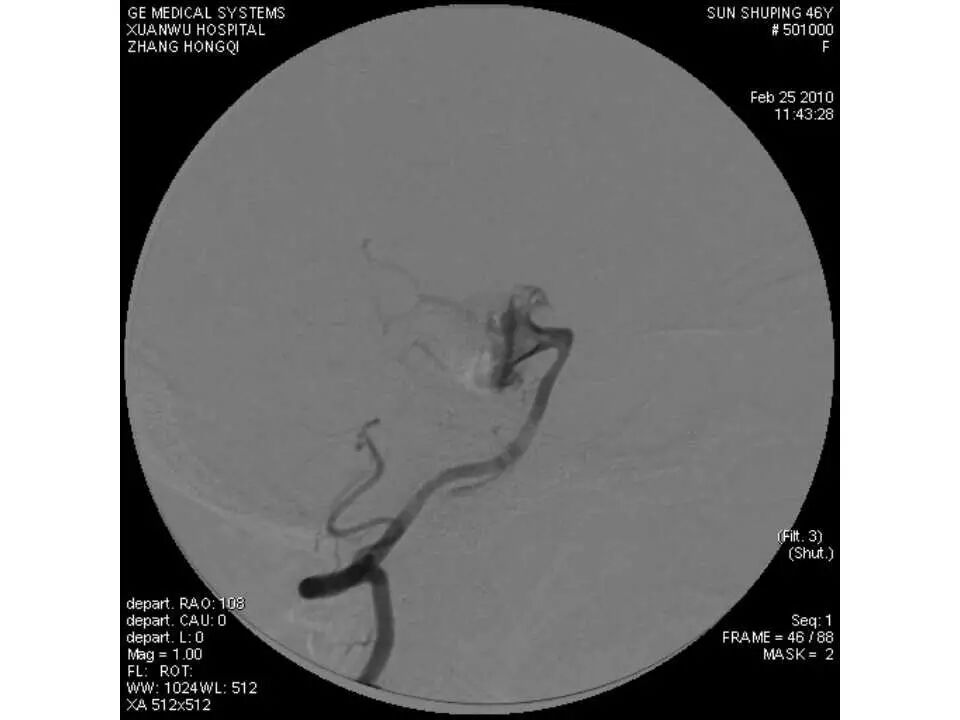

今天为大家分享的是“强生医疗CNV-神经介入专栏”第十五期,由首都医科大学宣武医院何川教授带来的“颅内动脉瘤介入治疗”精彩讲课视频及PPT,欢迎观看、阅读。文章仅代表作者个人观点,如有不同见解,欢迎同道斧正!